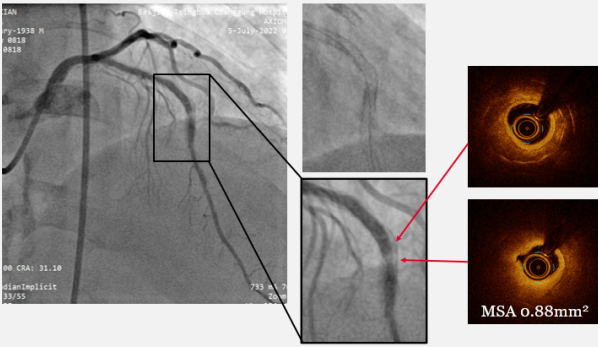

LAD介入治疗过程:首先在Finecross微导管支撑下尝试Fielder XT导丝不能通过病变,更换Gaia 2导丝,通过病变后,使用2.0*20mm球囊预扩后行OCT评估。发现支架内弥漫性再狭窄,最小支架内管腔面积(MSA) 0.88mm²,狭窄处可见双层金属支架影,增生斑块为环形钙化病变。(如图4

图4:LAD 预扩张后OCT检查

随后,我们选择3.0*12mm Shockwave冲击波球囊通过LAD支架内再狭窄伴钙化病变部位,根据标准操作流程,球囊压力充盈至4atm,先后触发80次脉冲击波(8个周期),实施钙化斑块碎裂术,并间断将球囊充盈压升至6atm维持10秒左右,对治疗段进行低压球囊扩张成形,随后通过OCT及冠脉造影融合技术证实, MSA:1.85mm²,支架内钙化环被打开,震波深达0.52mm,换用3.5*15mm NC 耐高压球囊以20-24atm扩张后,测得MSA:3.21mm²,扩张仍然不理想。介入团队经商定后,决定更换3.5*12mm Shockwave 冲击波球囊再次进行8次周期的斑块碎裂术,事后以3.0-3.25-3.5mm NC球囊高压充分高压扩张,通过OCT证实MSA达到4.56mm²(如图6,7)。造影提示支架内血流通畅,残余狭窄<10%,前向血流恢复TIMI 3级,最终结果如图8。患者术后胸痛症状明显缓解,安全出院。

图6:Shockwave冲击波球囊治疗过程

图7:3.0*12mm与3.5*12mm Shockwave冲击波球囊治疗后OCT影像对比